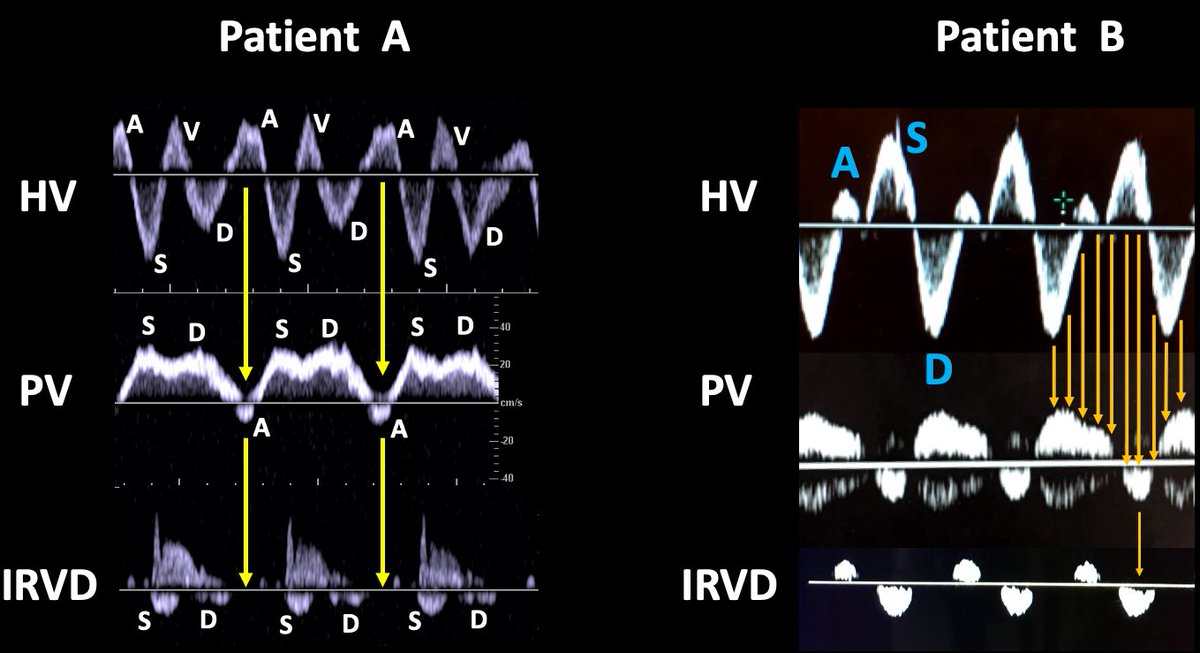

You are asked to evaluate 2 patients with venous congestion and kidney injury.

Which patient is more congested?

I would argue congestion is pretty similar in both cases: Portal Vein has reverse flow and RVSI (Renal Venous Stasis Index) is > 0.5

Strictly speaking pt B has worse congestion, more flow reversal and higher RVSI

Patient A has a normal RA filling pattern

Patient B has severe TR with HV "S" wave reversal

While both patients have a large retrograde flow towards the organs, it is very possible patient B has a lower absolute preload value (because of the CVP morphology in severe TR)!

Hence, it is my opinion that patient A is more likely to tolerate aggressive decongestion!

In these particular examples this was actually the case!

For clearness: I don’t pretend to know what the actual preload is in each case. The point is that in order to normalize PV/IRV it would take a greater decrease in preload for pt B since the pressure wave traveling backwards (CV fusion) is further away from that filling the RV

Hence, aiming to normalize PV/IRV Doppler alterations would be better tolerated for patient A. In patient B, flow alterations might be imposible to completely normalize as is our experience with PAH and severe TR!